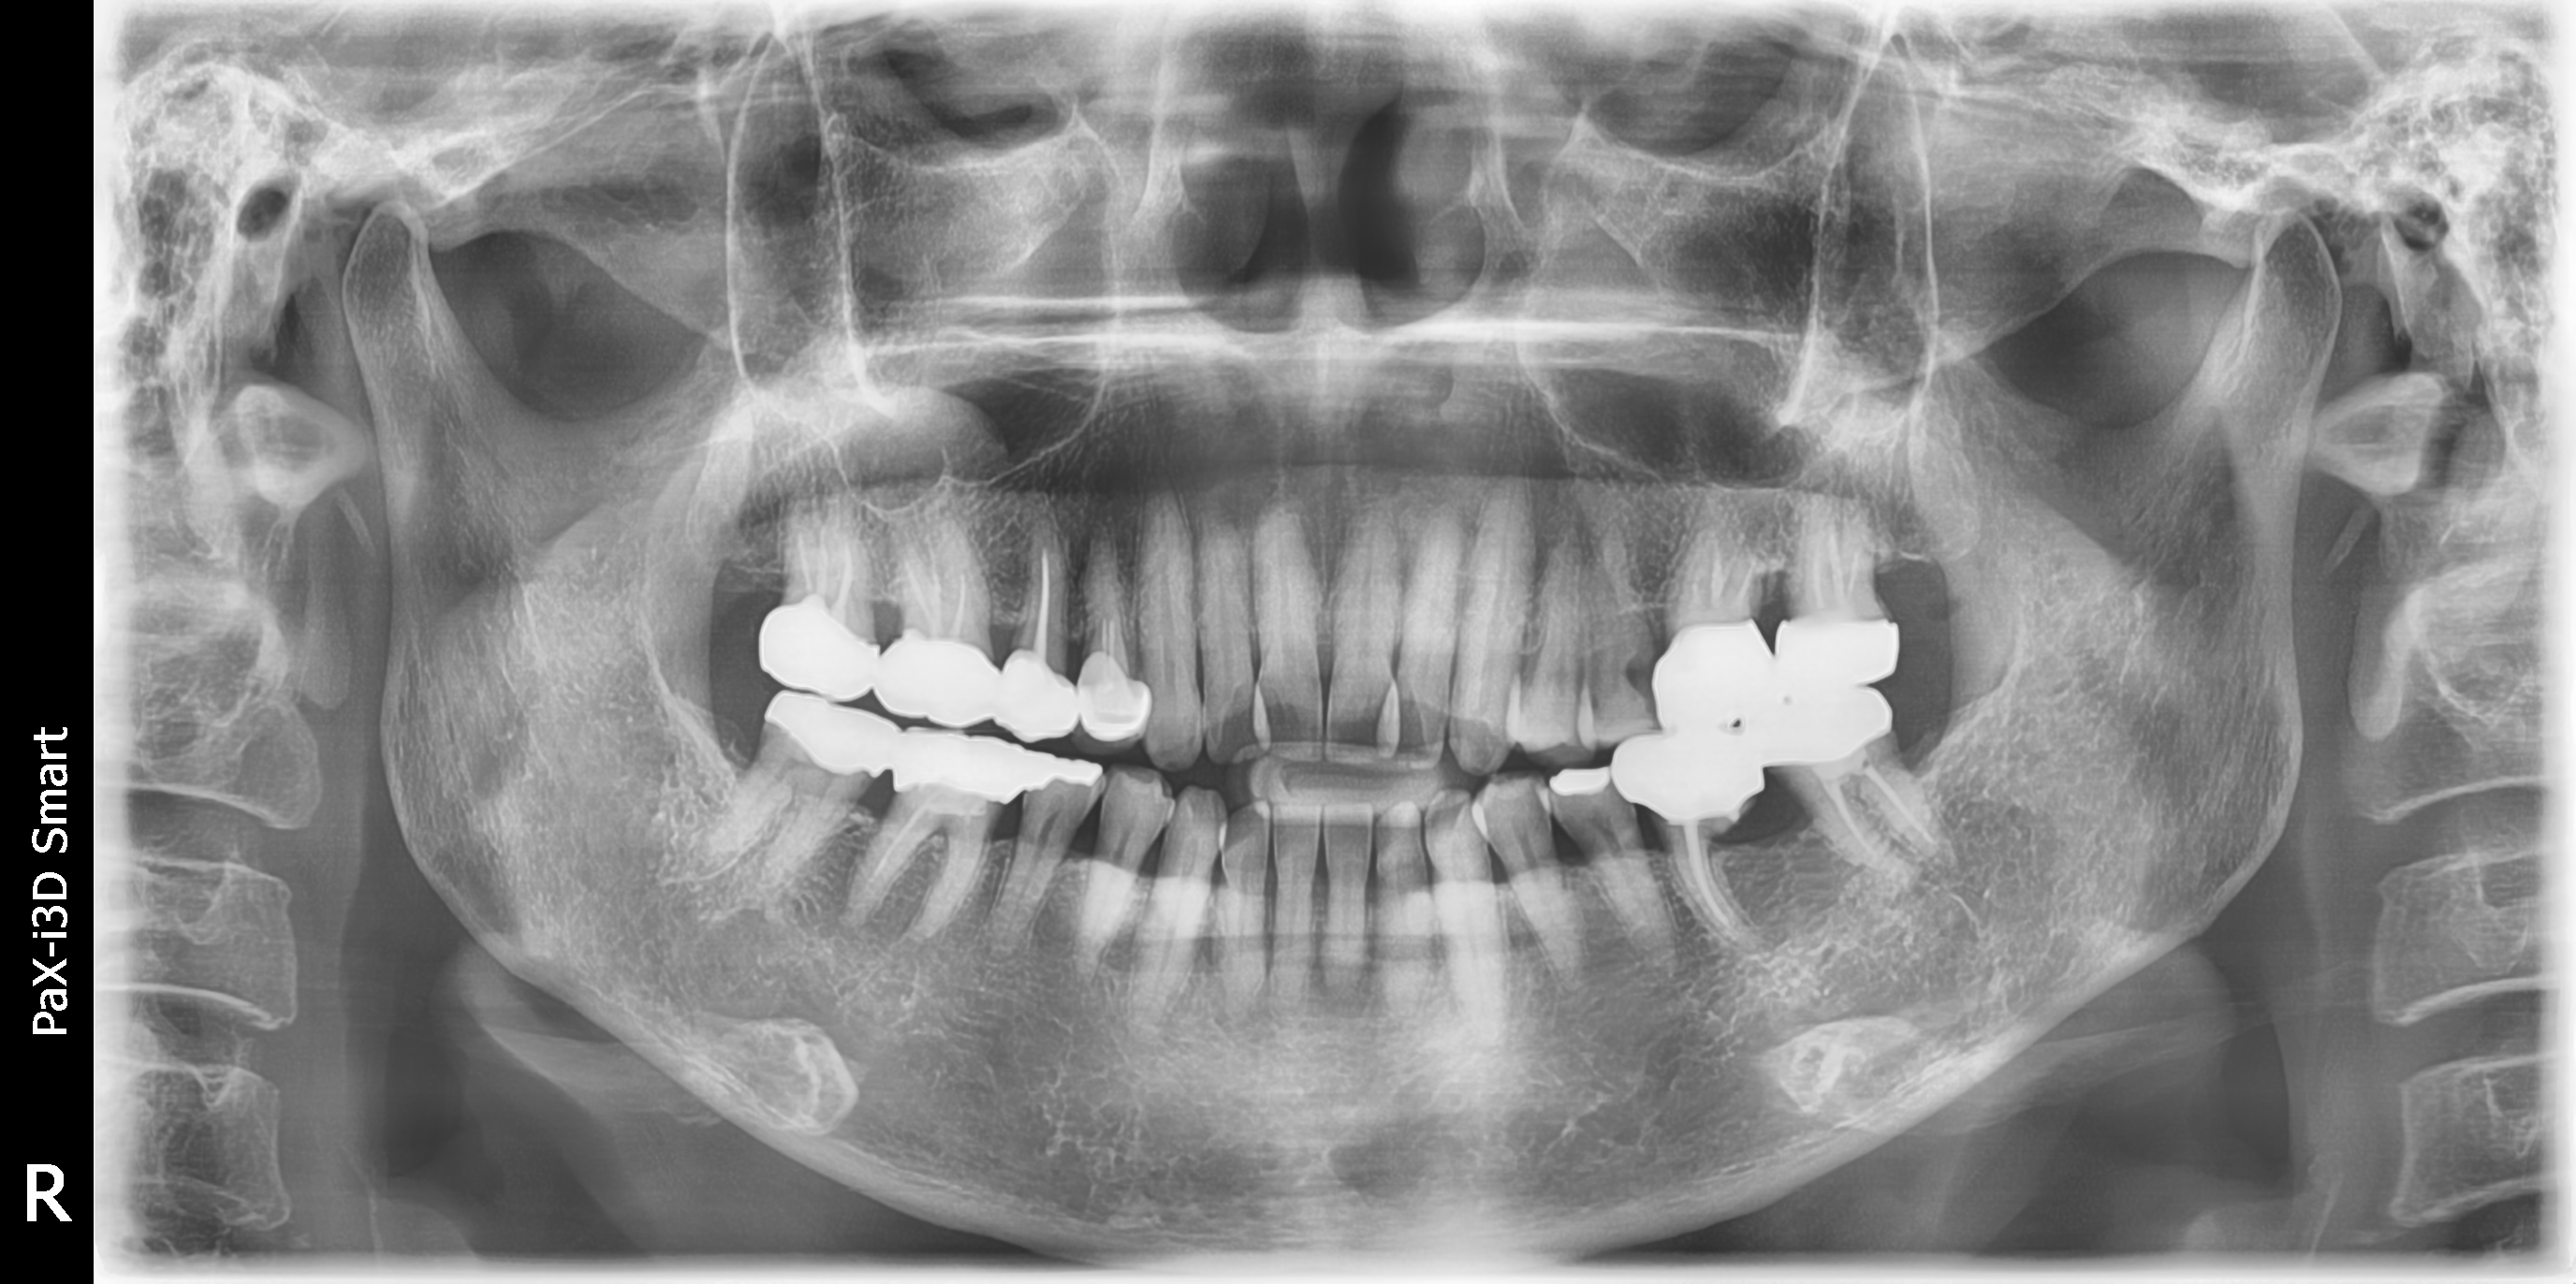

The patient is a woman in her 60s who came for a dental visit due to discomfort with tooth number 46.

Tooth number 36 shows unfavorable conditions in the distal root area.

Tooth numbers 36 and 37 are connected by a prosthesis, and there is no mobility. After discussing with the patient, it has been decided to remove only the distal root for now.

This is the radiograph taken approximately 7 years after the procedure.

There are no specific issues, and it is functioning well.